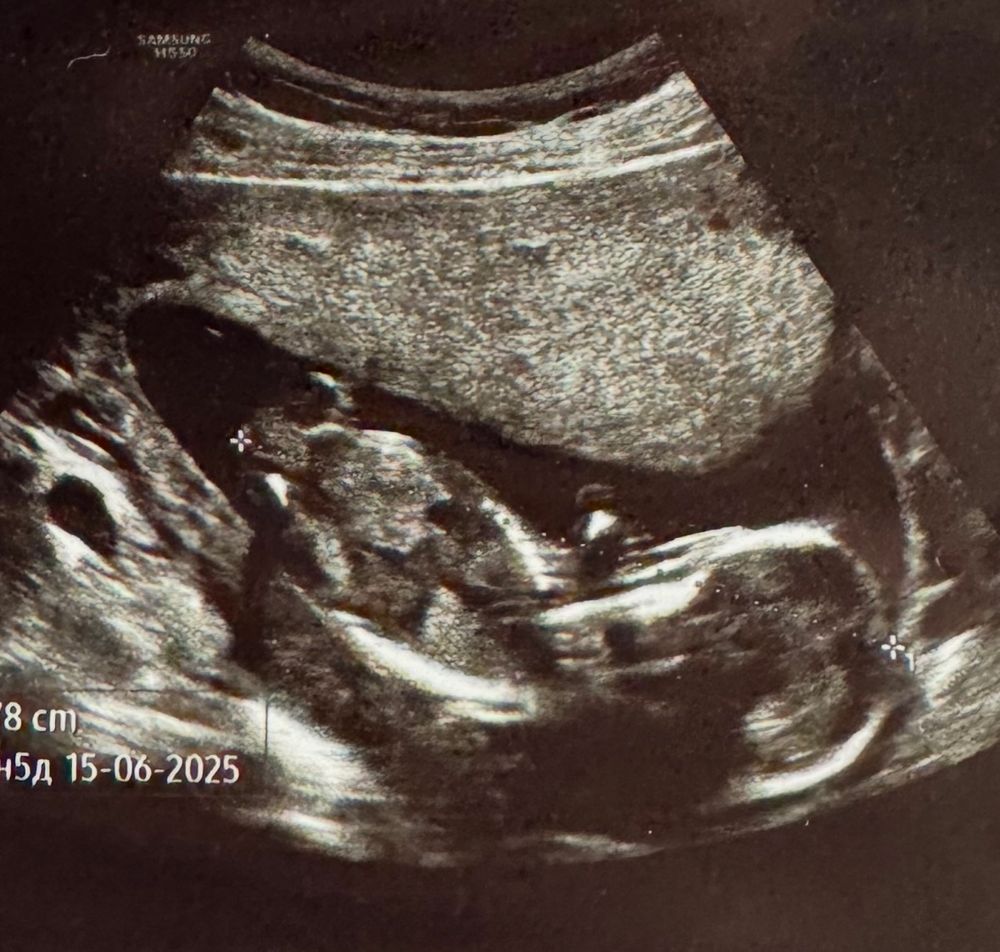

Виолетта, Поздравляю🥰 Пусть растет здоровым!) У меня аналогичная ситуация с вами, на 1 скрининге тоже сначала сказали девочка, потом ближе к 15н другая узистка предположила мальчика

Виолетта, и фото узи у нас почти похоже) Но только у меня чуть качество хромает😂😅 Но можно тоже что-то да разглядеть( кверху торчит как мне кажется этот бугорок) Изображение

Узи 16 недель (мальчик девочка?) ваше мнение мамочки ?)) У кого сейчас срок 11-13 недель,